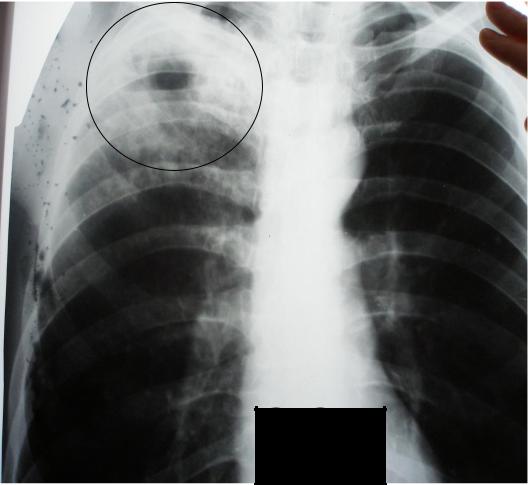

Симптомы и лечение инфильтративного туберкулеза легких

Раздел: Снимки-откровения